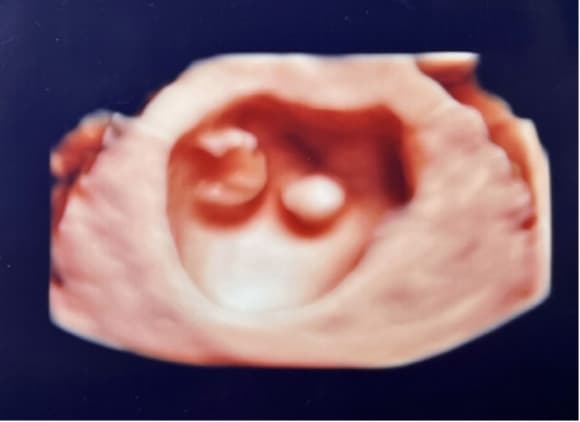

4Dエコー外来

• 妊婦健診の中でいつでもご希望の時に、お腹の中の赤ちゃんの状態を立体的に、そして動きまでリアルにご覧いただける超音波技術を用いた4Dエコー外来が受診できます。

• お腹の中のお子さまの様子を鮮明にご覧いただくことが可能です。(希望者のみ:2,160円/回)

※当日の胎児の向きや、姿勢によって必ずしも顔がはっきり見られるとは限らないため、費用は見えたときのみいただいております。

4D胎児エコー写真

(10週)

(12週)

一卵生双胎